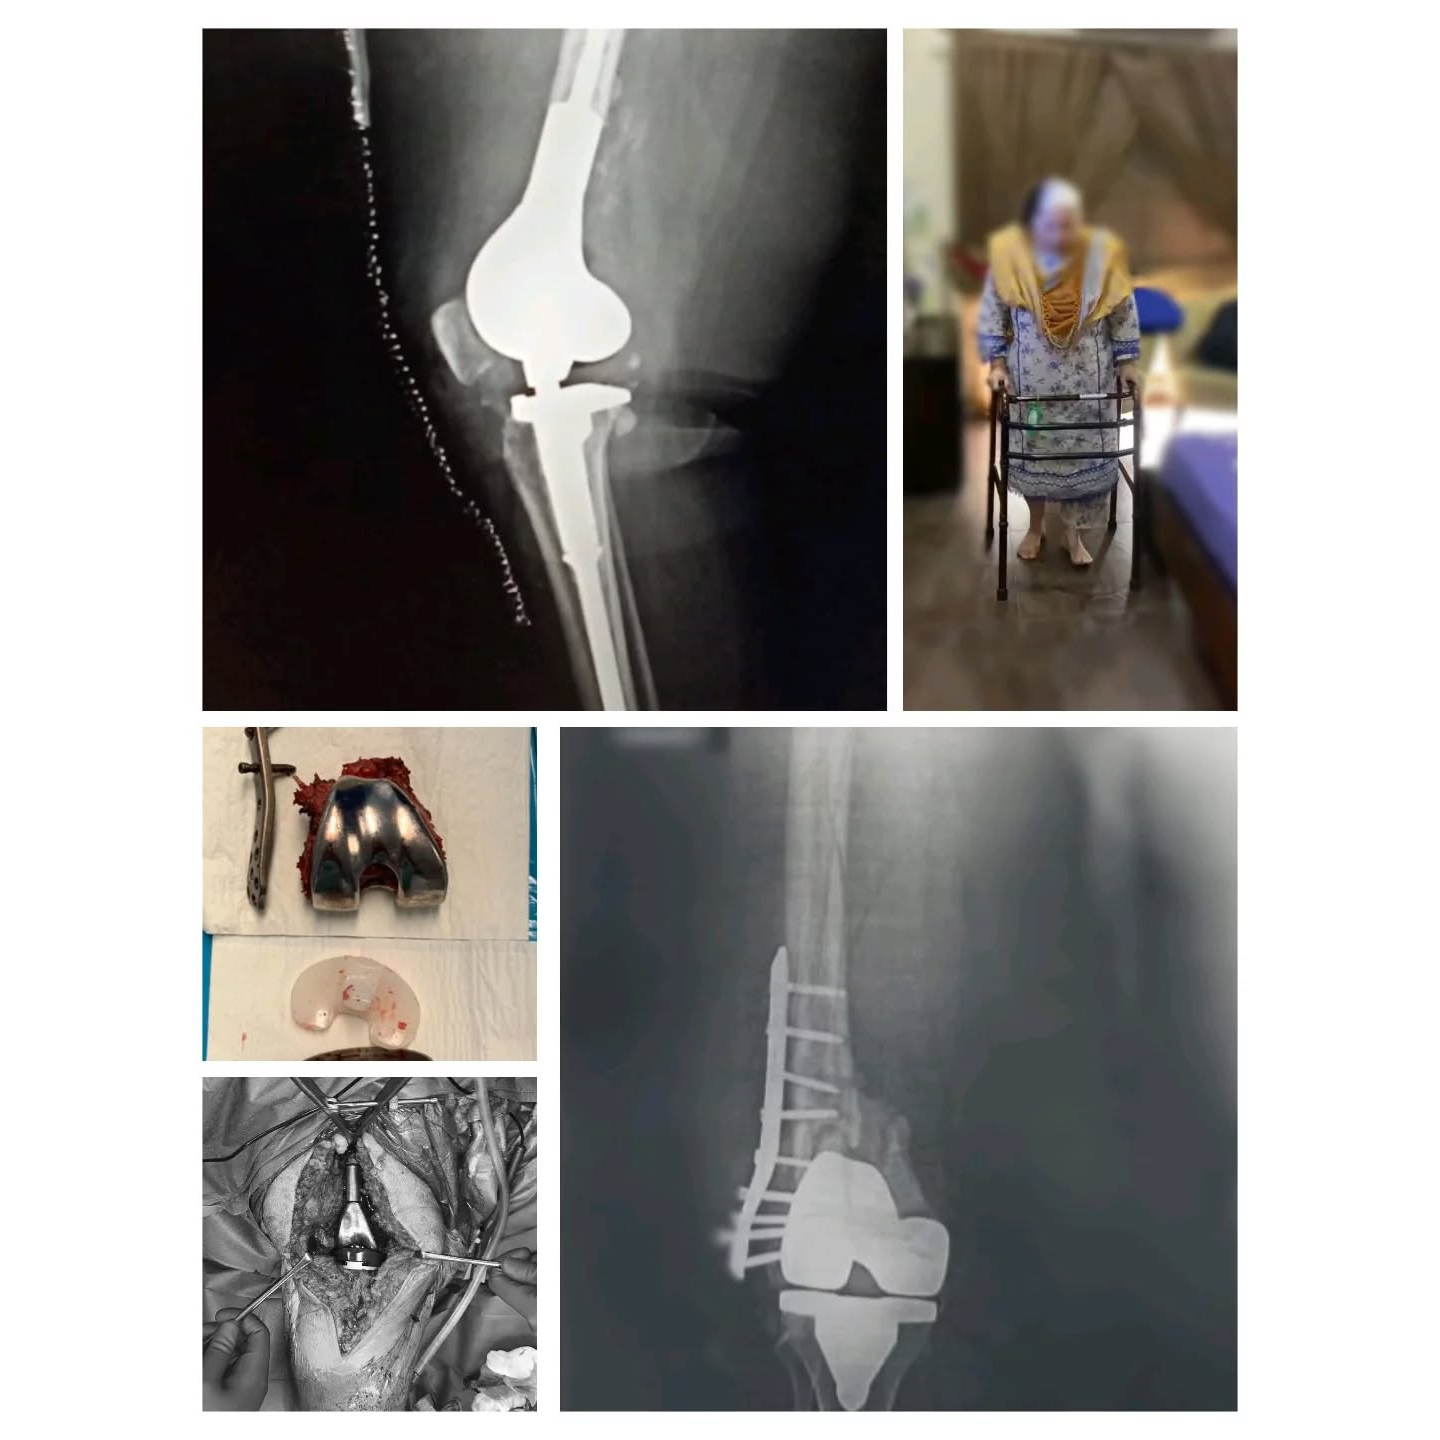

Distal femur replacement surgery